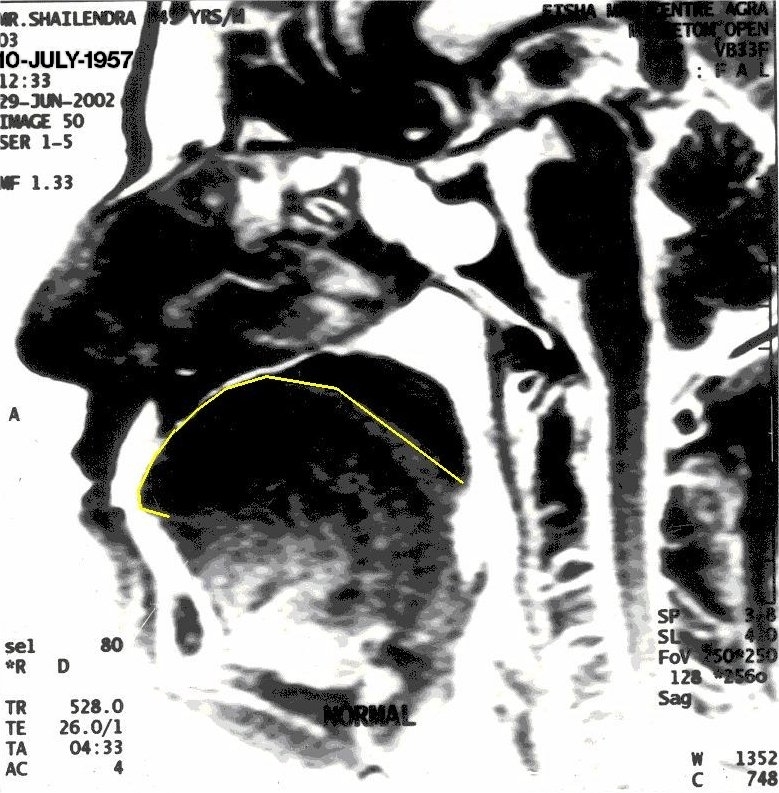

Before Khechari Mudra

The position of tongue is outlined in yellow